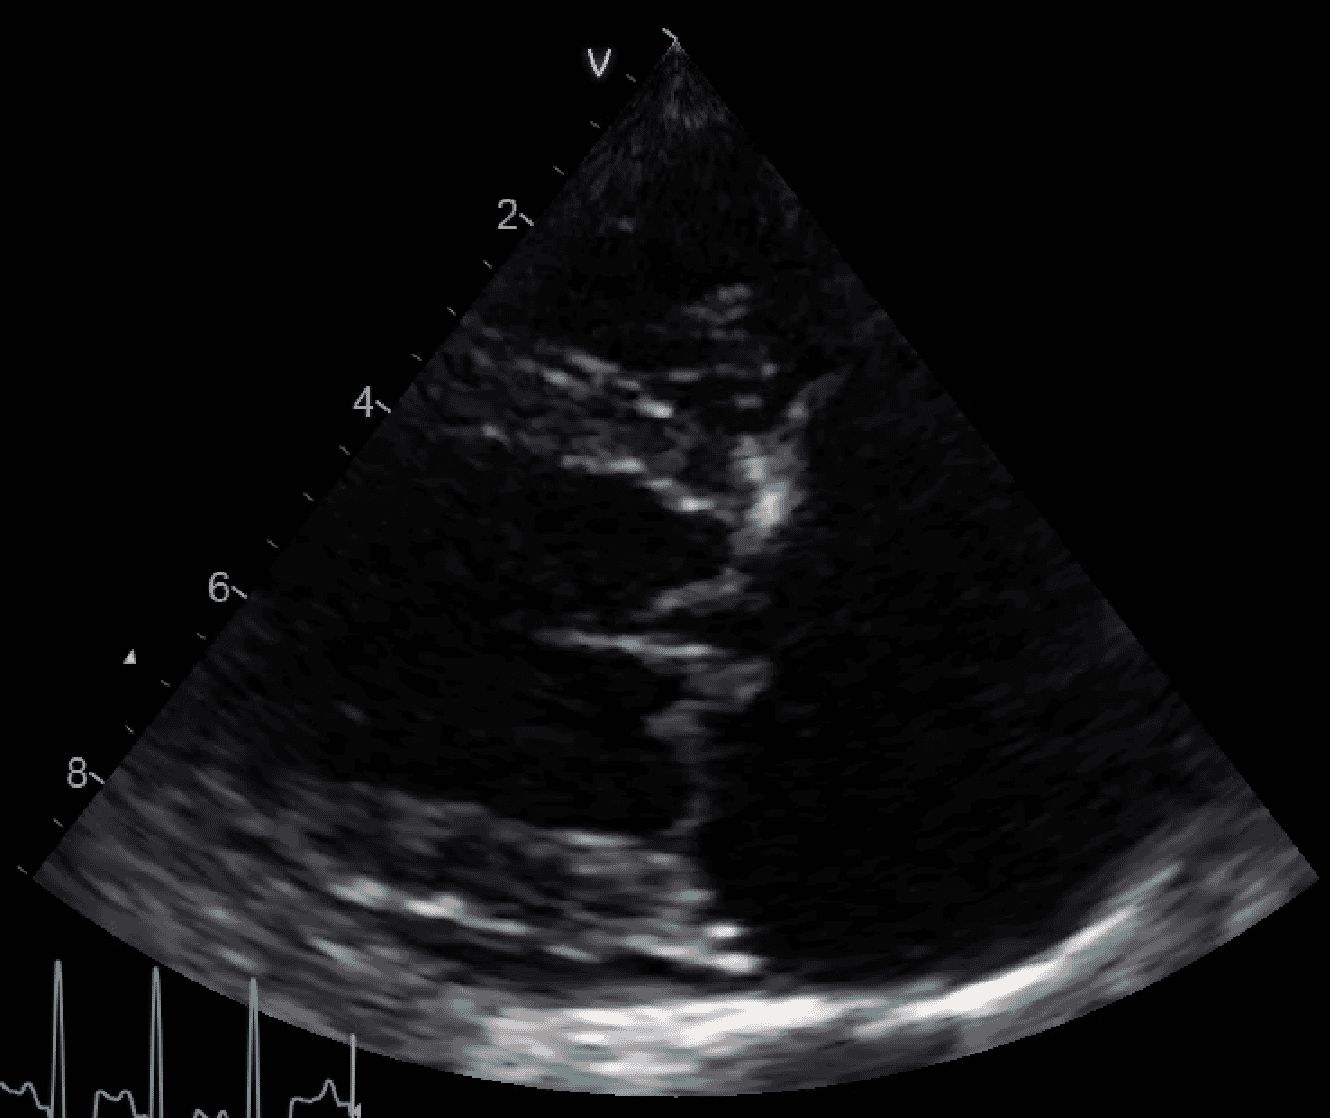

The aim of treating a dog with MVD intensively is to reduce left atrial pressure, and therefore reduce pulmonary vascular pressures and reduce the drive to produce more pulmonary oedema. If parenteral diuretic therapy is not successful, either as boluses or as a continuous rate infusion, then the next best way of achieving this is to increase forward flow (thereby reducing the severity of mitral regurgitation). To do this, systemic vascular resistance should be decreased to reduce afterload. Pimobendan is an arteriodilator, so should have already provided us with some assistance in this department, but if the patient is not responding then there is still more that we can do.

The dog with DCM and persistent pulmonary oedema

Dilated cardiomyopathy causes poor output in combination with pulmonary oedema. Mitral regurgitation may or may not be present, but the most important factor impeding this dog’s recovery is poor systolic function and therefore low cardiac output. Some clinicians express concerns about administering diuretic drugs to patients with hypotension and pulmonary oedema, fearing renal injury or worsening of hypoperfusion. However, increased preload (blood volume) in dogs with severe systolic dysfunction can itself reduce cardiac output. If preload is reduced with furosemide, output should increase (or at least not reduce significantly) in DCM ( Figure 5). Some heart diseases, such as mitral stenosis, are relatively preload dependent, so dogs with this problem (rare outside of the English Bull Terrier) should receive more cautious diuretic doses.